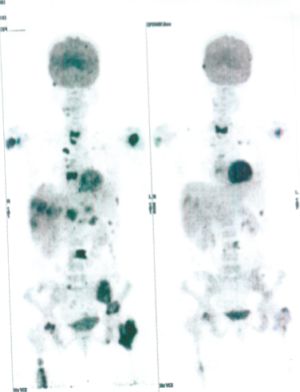

Below are some of the cases, from more than 80 cases we have treated so far with good results. When reading the PET/CT scans, the picture on the left is before treatment, and the picture on the right is after treatment. The intensity of black represents the activity of the cancer, but some black areas are not cancer: brain, heart, radioactive urine in bladder. For the heart, the intensity of black depends on the number of hours of fasting: if more than 10 hours, the heart is not even black, but if fasting is less than 6 hours, it is very black. The intensity of black in the brain can be variable in different scans depending on the brain activity at the time of the scan. The intensity of black in the radioactive urine can also be variable due to the hydration of patients and the time of injection of diuretic.

CASE NO: 1

(HEPATOCELLULAR CARCINOMA + STOMACH CANCER)

A middle-aged women who is very thin and very weak, can hardly walk, lying in bed most of the time. She saw a cancer specialist in a top hospital who discovered that she had massive hepatocellular carcinoma, and another cancer in the stomach. Given that hepatocellular carcinoma is incurable and stomach cancer is very difficult if not impossible to cure without surgery, she was told that nothing could be done for her. She came to ask us to help her. After just 4 treatment, the hepatocellular carcinoma went into remission, and the stomach cancer (arrow) became less active. Until today, more than 6 months later, the hepatocellular carcinoma is still in remission.

CASE NO: 1 - A FEW MONTHS LATER

A few months after successful treatment for hepatocellular carcinoma, and partially successful for stomach cancer, the PET/CT scan showed the stomach cancer becoming very active, with several metastases to the parts of the liver not previously involved by hepatocellular carcinoma. After a few treatment, all the active stomach cancer lesions in the stomach and in the liver went into remission.